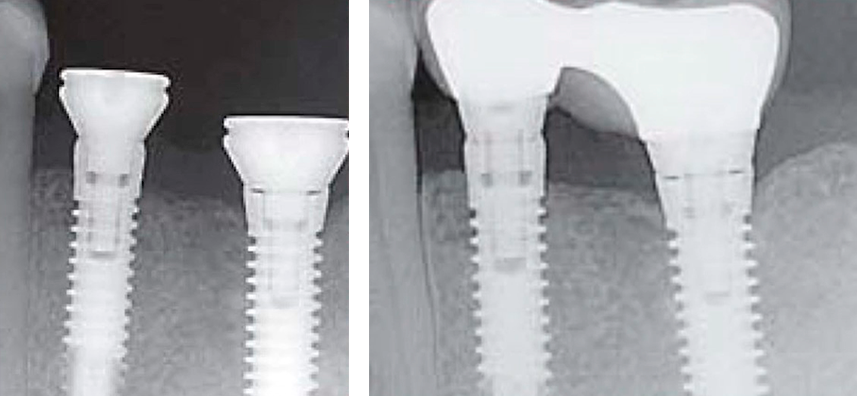

The illustrations below show the appearance and application principle of V-Type multi-unit abutments.

Therefore, Bone Level implants combined with screw-retained prostheses remain the “gold standard”, with modern multi-unit abutments providing solutions for complex cases.